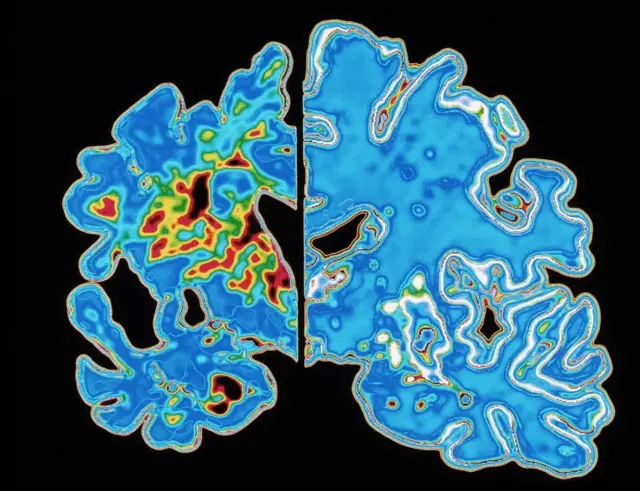

Chanzo cha picha, SPL